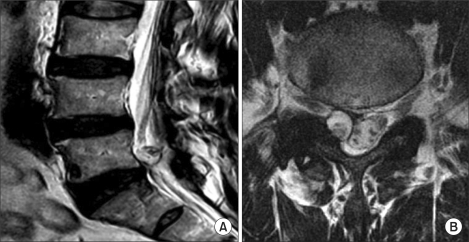

MRI showing L4-5 synovial cyst compressing the thecal sac and right nerve root. Sagittal (left) and axial (right) T2-weighted views demonstrating the cyst arising from the facet joint.

Unfavorable features (lower rupture success):

• T2 hypointense or mixed signal: Chronic, organized cyst material

• Thick wall: Fibrotic capsule resists rupture

• Calcified walls: Cannot be ruptured with pressure

• Gas-filled cysts: Vacuum phenomenon within the cyst

Unfavorable for rupture:

• Thick dark wall on T2-weighted images

• T2 hypointensity or mixed signal within the cyst

• T1 hyperintensity (suggesting blood products or proteinaceous material)

• Calcification within the cyst wall (seen on CT)

• Internal structure or debris apparent within the cyst